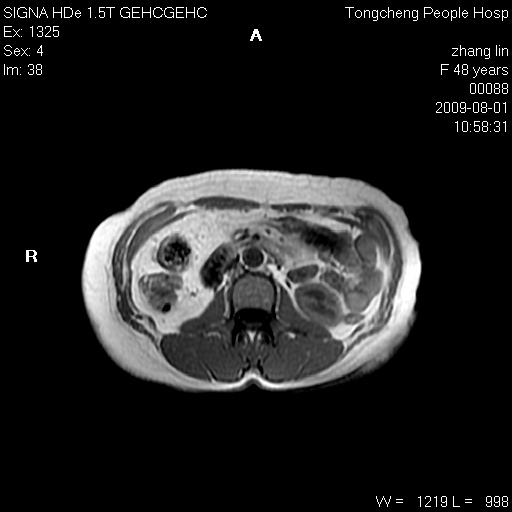

女,48岁。健康体检,彩超发现右肾占位性病变。平素健康。

临床诊断:右肾占位性病变,性质待定(囊肿?肿瘤?)。

上中腹部mr平扫+增强扫描,图像如下:

右肾上极见一类圆形病灶,t1wi呈等信号t2wi呈等高混杂信号,三期增强无强化,边界清---考虑囊肿出血。

同反相位均表现为等信号,病变无强化,考虑含蛋白的囊肿可能,弥散加权相或许有些帮助,

慢性胆囊炎